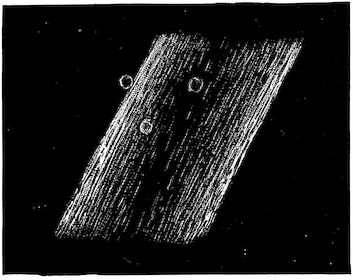

Fig. 10.—Dressing for fracture of the horn.